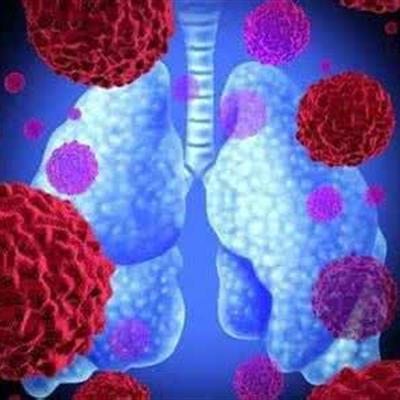

Gastric cancer, liver cancer and lung cancer are not only common diseases with high mortality, but also one of the most common malignant tumors in human body. This terrible disease deprives many people of their precious lives year by year. For patients, early treatment is needed. Why can advanced lung cancer coma, now let's understand.

First: when lung cancer is advanced, it is easier to produce coma symptoms. If the patient is comatose, then the cachexia is often studied seriously, and even the patients with this disease have the trend of lung cancer brain metastasis. There are cancer cells in the brain, so coma is more likely to occur at this time.

Second: advanced lung cancer patients need to do some head CT examination to see if there is brain metastasis. And you can go to a big hospital for MRI diagnosis. Of course, once a patient has cancer, he can't eat hair or goose.

Third: once the patients with advanced lung cancer have the symptoms of coma, they can't take medicine casually. At this time, we need to use drugs to reduce brain edema under the guidance of doctors. Then you can use mannitol to reduce blood pressure.

The patient needs to do some further head CT examination to see if there is brain metastasis. And you can go to a big hospital for MRI diagnosis. Of course, once a patient has cancer, he can't eat hair or goose.